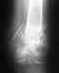

Добрый день!У меня вопрос касательно аппарата Илизарова.После снятия стержня который гноился, гной не перестал течь. Выходят мелкие кусочки кости. Прошел уже месяц после демонтажа. Ни во время стадии носки ни после ни температуры ни болей не было. Это что-то серьезное? Скажите, пожалуйста. Сейчас прикладываю гипертонический раствор. Всего доброго.

Это нередкая неприятность. Все Вы делаете правильно. Течение обычно доброкачественное, канал очистится и закроется. Если нет - надо обработать (почистить) хирургически. Вас, надо полагать, наблюдают врачи, пусть держат ситуацию под контролем.